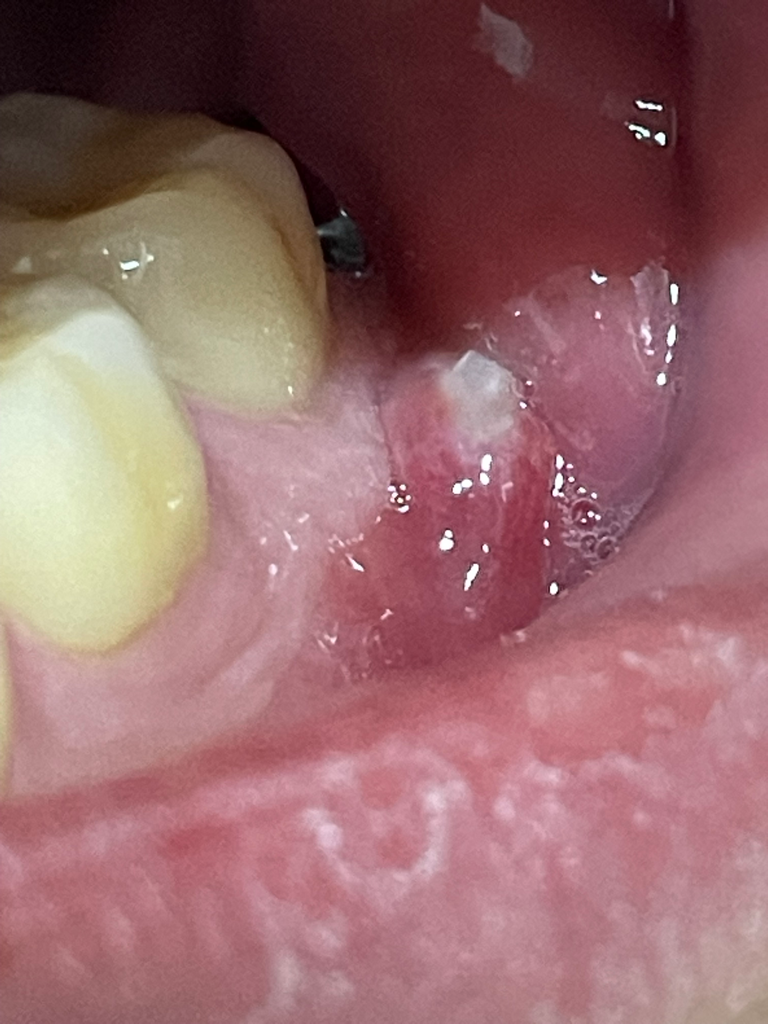

잇몸에 뭐가 생겼는데 이게 뭔가요?

사랑니를 뽑았는데 그 앞 치아 옆에 큰 염증 같은게 났습니다 그런데 끝이 하얀색인데 약간 딱딱함이 느껴집니다 혹시 고름이나 치아 같은 건 아닐까요?

• 안녕하세요. 김철진 치과의사입니다.

추측해보자면 치아의 뿌리일수도 잇고 잇몸뼈 조각일수도 잇으니 치과에 가셔서 체크를 받아보시는게 좋을것같습니다.